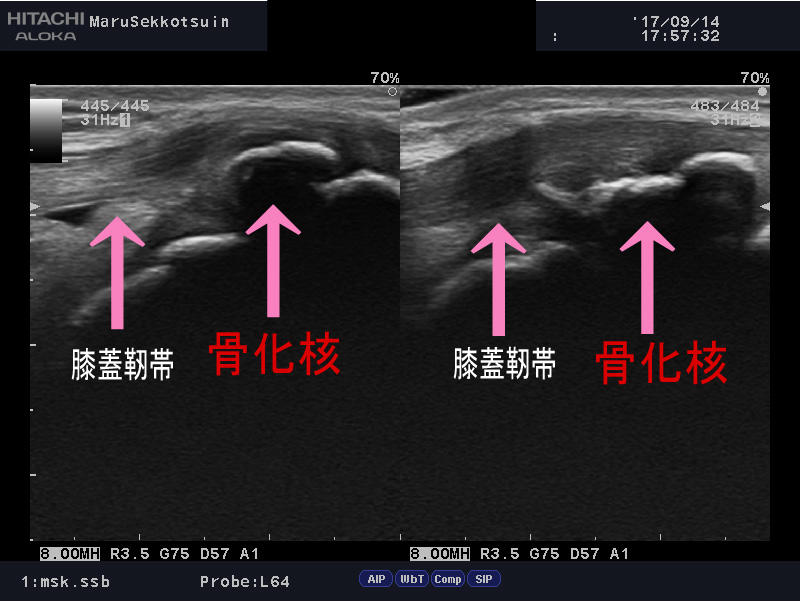

しっかり問診し、触診し、最後にエコー検査。

「オスグッド・シュラッター病」

病態を申しますと、

10歳~15歳のキッズアスリートに多く、

特に男児に多く診られます。

この時期は成長期であり、骨の成長と筋肉の成長のバランスが、

とても悪い時期でもあります。

お皿の下、脛骨粗面と言われる、骨の出っ張り部分が、

大腿四頭筋(モモの前の筋肉)の牽引力によって、

腫れてきたり、熱を持ち、痛みを誘発します。

この脛骨粗面の周囲は成長軟骨が多く存在し、

力学的に柔らかく弱い部分で、痛みを誘発し易い場所になっています。

その成長軟骨部分は年齢によって成長の段階があり、

まる接骨院では超音波観察装置で、骨の状態を、

画像でどの段階かを確認しながら治療を進めていきます。